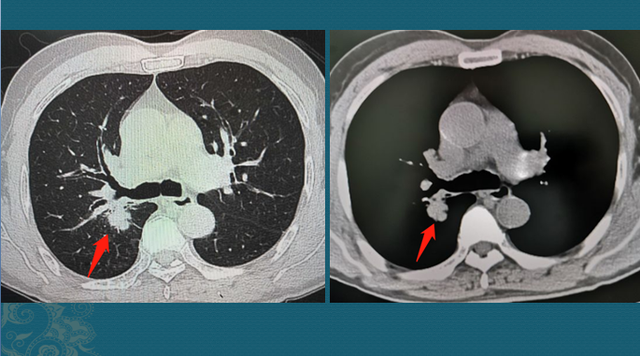

这位病人厥后做了4个周期化疗(吉西他滨+奈他铂),效果很是好,在第三周期化疗后做了一次CT复查,肿瘤显著缩小:

事实上,晚期肺癌经由 综合治疗,生涯 5年以上的病人越来越多了,而且能保证很好的生涯 质量。无论选择哪种治疗方式,都可以向主治医生咨询大致的用度,预期可能到达的效果等,实事求是 。在能力允许的条件 下,既阻止 人财两空,也不容易 松手 ,事实 家人的生命只有一次。